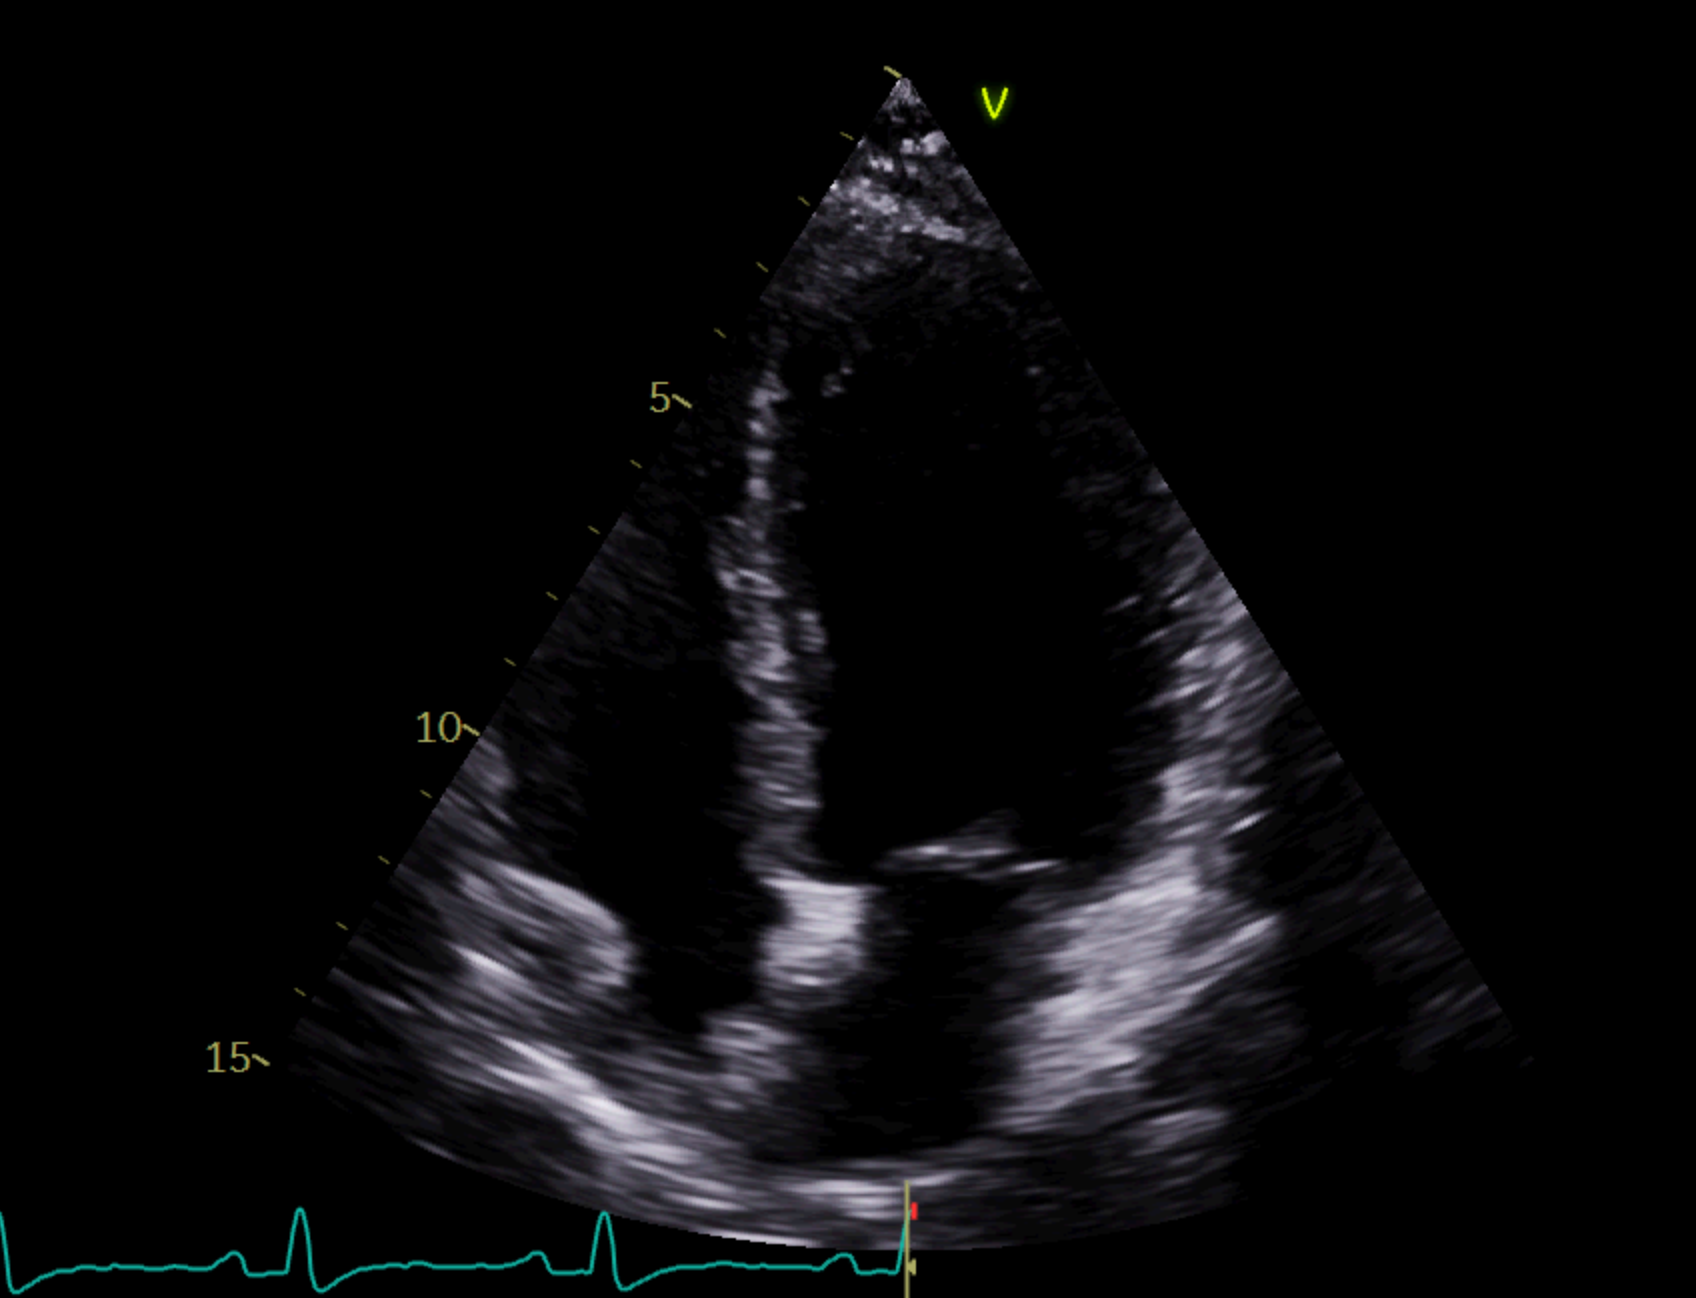

Ecografía a pie de calle: hipercontractilidad de bases e hipocinesia de segmentos medio-apicales. Fracción de eyección del ventrículo izquierdo conservada. Sin derrame pericárdico. Impresiona engrosamiento de pared libre de ventrículo derecho.

Posteriormente durante su ingreso perdura nuevo episodio de dolor torácico y se determina Troponina en pico de 5.989 ng/L. Se realiza ecografía y ventriculograma que sugieren STT. A consecuencia de esto, la estenosis de la DA supondría un hallazgo y no la causa principal del dolor torácico.